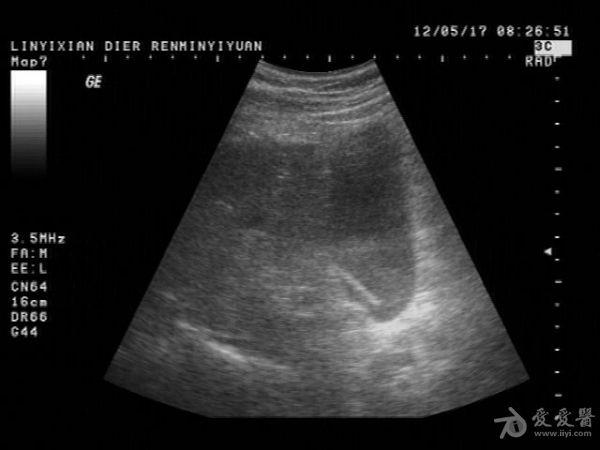

患者男性,57岁,十多年前曾患“肝炎”,近一年在它院曾诊断为:肝硬化。一月前在市医院治疗发现有腹水形成并发现有“腔梗”。古来我院就诊。B超提示:肝脏病理声像(肝光点增粗、肝硬化声像)胆囊图像如图。腹盆腔未及游离暗区回声。

这个胆囊颈部的暗区可以称“胆囊憩室”吗?